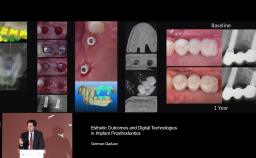

My ITI - German Gallucci

Public ITI profile page of

German Gallucci